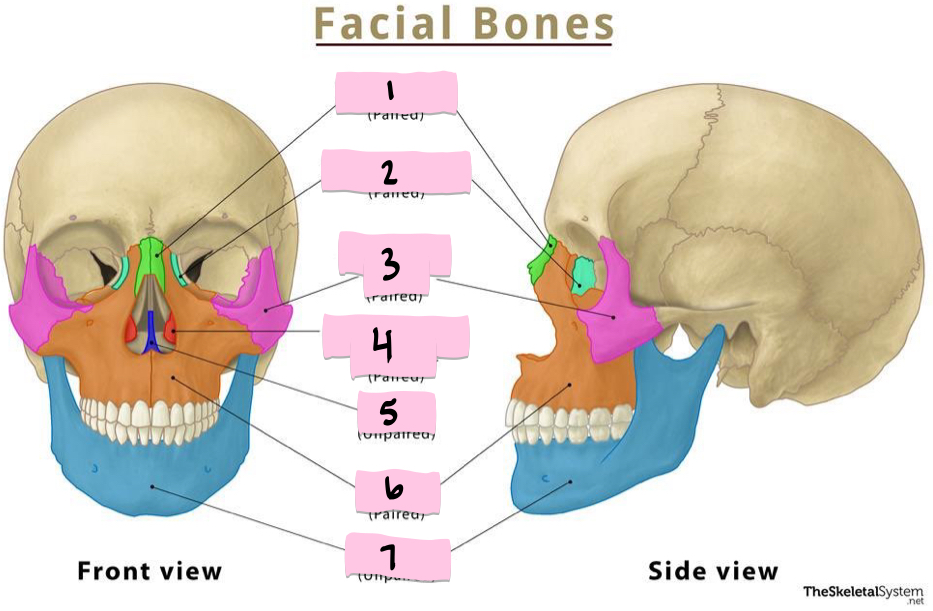

What is 1 pointing to?

Nasal bone

What is 2 pointing to?

Lacrimal bone

What is 3 pointing to?

Zygomatic bone

What is 4 pointing to?

Inferior nasal conchae

What is 5 pointing to?

Vomer

What is 6 pointing to?

Maxilla

What is 7 pointing to?

Mandible